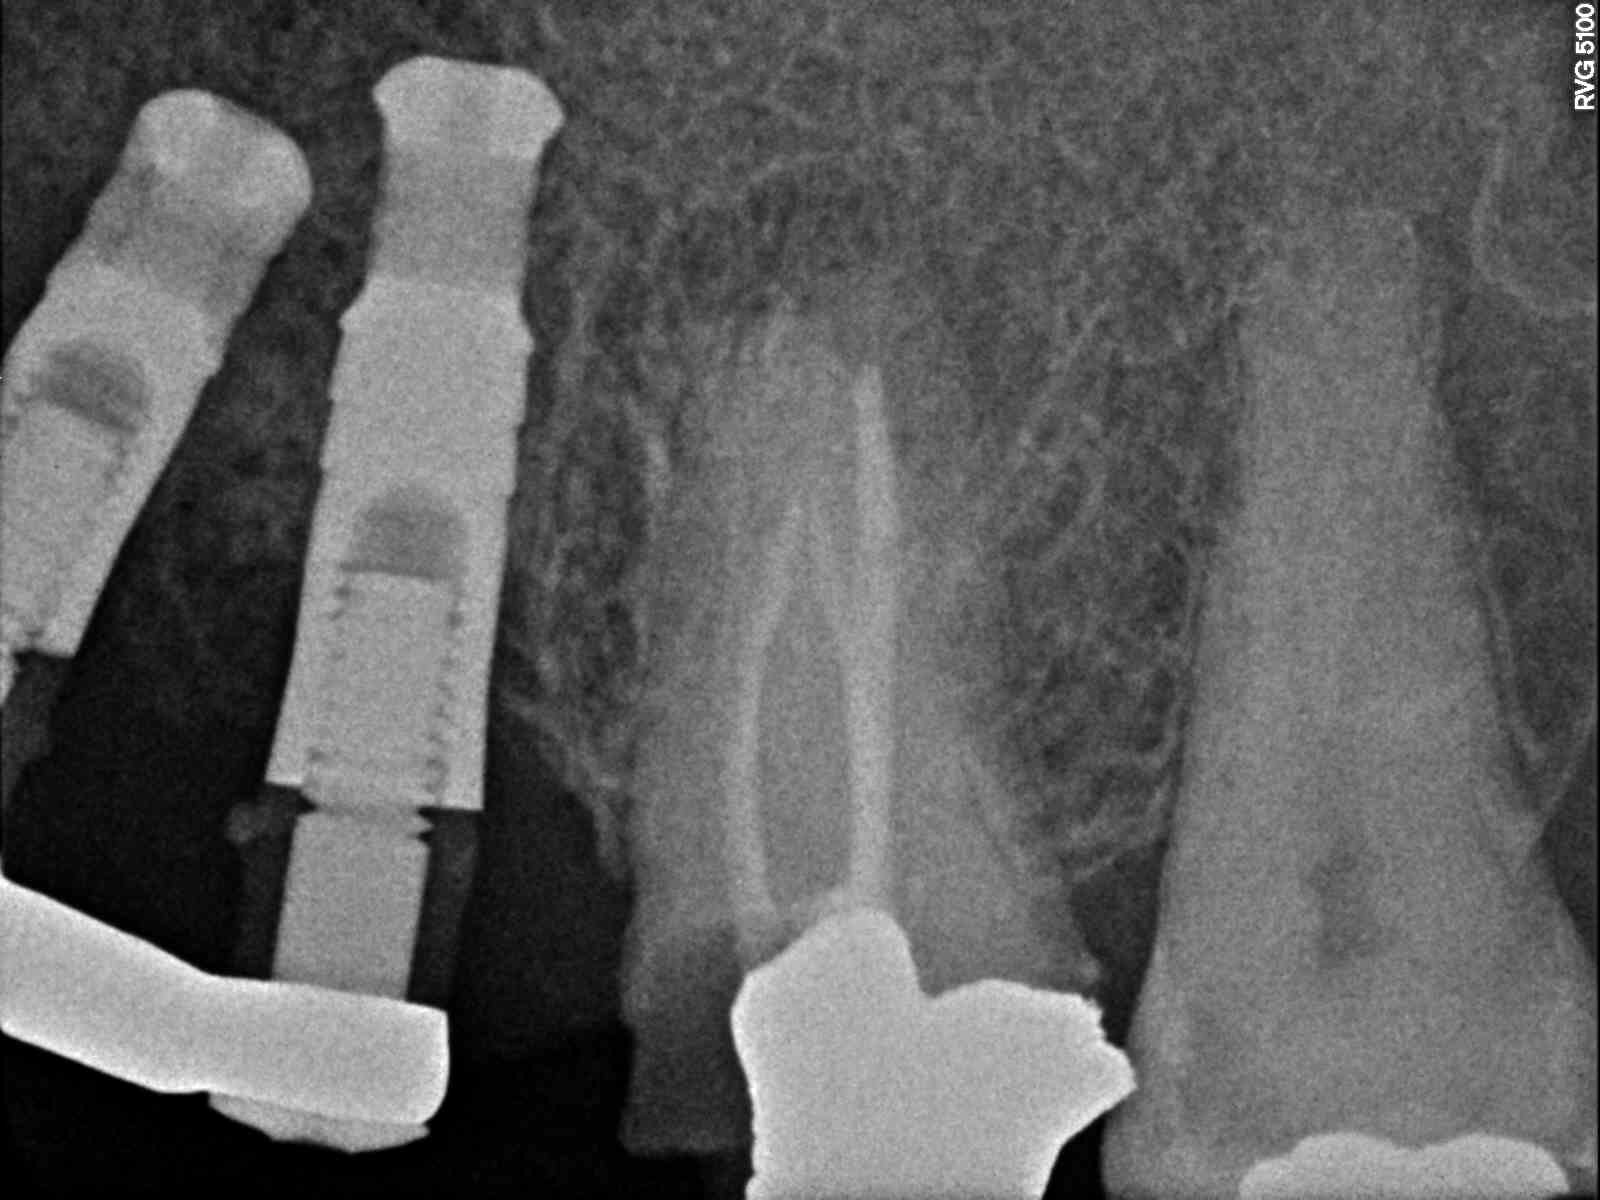

Buenos días apreciadxs compañerxs! El otro día acudió a la consulta una paciente, indicando que hacía 3 años que llevaba los implantes en boca. No tiene pasaporte, y la clínica [...]

El 13 es compatible con Sweden & Martina Outlink 3,3. Los otros he probado distintos transfers y no consigo que adapten. Tiene prótesis fijas sobre ioi cementadas y necesito levantarlas [...]